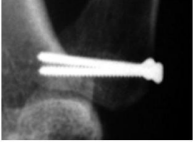

- Nắn mở và cố định trong: gãy di lệch không thể nắn được (mảnh vỡ > 20% mặt khớp) [1]

Sử dụng kỹ thuật mổ ORIF (theo Wagner)

Một vis và đinh Kirchner: mảnh gãy ít hơn 1/3 mặt khớp

Hai vis hoặc kết hợp 2 vis và 1 đinh Kirchner: mảnh gãy chiếm hơn 1/3 mặt khớp